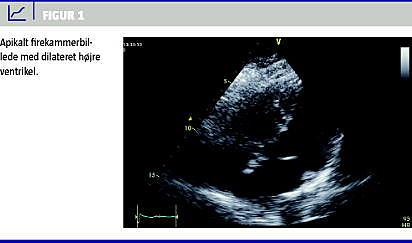

Der blev foretaget focus assessed transthoracic echocardiograph y (Figur 1 ), som viste en dilateret højre ventrikel med kompression af venstre ventrikel. På mistanke om central lungeembolus blev der påbegyndt højdosis antitrombotisk behandling med intravenøst givet injektion af dalteparin 200 IE/kg.